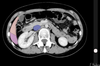

yellow: segment III

green: segment IVb

peach: segment V

lilac: segment VI

purple:

blue:

yellow:

peach:

lilac: